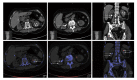

Dual-energy computed-tomography (DECT) has been suggested as the method of choice for imaging urinary calculi due to the modality's high sensitivity for detecting stones and its capability of accurately differentiating between uric-acid (UA) and non-UA (predominantly calcium) stones. The clinical significance of the latter feature relates to the differences in management of UA vs non-UA calculi. Like calculi, ureteral stents are assigned color by the dual-energy post-processing algorithm, which may lead to improved or worsened stone visualization based on the resulting stent/stone contrast. Herein we depict the case of a nephrolithiasis patient with bilateral stents, each with different color, clearly displaying the effect of stent color on stone visualization. Further, three-dimensional reconstruction of the DECT images illustrates advantages of this enhancement compared to conventional two-dimensional computed tomography. The resulting stent/stone contrast produces an unanticipated potential advantage of DECT in patients with urolithiasis and stents and may promote improved management decision-making.